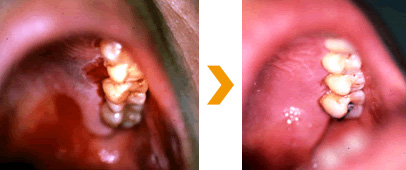

M.H. 様(67歳)男性

歯医者さんに歯茎をマッサージしなさいといわれたが、寝ていても膿が口の中に溜まるといって来院。3週間で膿が出なくなりました。炎症が無くなれば骨を丈夫にする薬をのんで歯を抜けないようにしていきます。